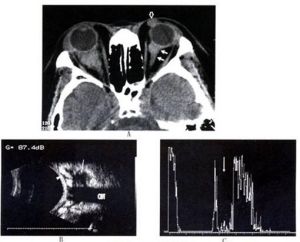

惡性淋巴瘤的病理診斷一經確定,為了解病灶的擴散情況,需要做全身檢查。體表的淋巴結經觸診可測定,腹膜後淋巴結可通過CT和腹部超音波診斷加以明確。CT和B超檢查也可明確肝、脾等腹腔內臟器的異常。

此外,對瓦爾代爾環受浸潤的病例,應到耳鼻咽喉科檢查、診斷,並做胃X線檢查。消化道發現淋巴結腫大時,應從胃開始直至大腸為止做全消化道方面的檢查,或做X線檢查,或做纖維內窺鏡檢查。當肺、肝、眼、腦、睪丸等臟器發現病灶時,要和相關臟器的專科醫生邊商量邊做有關檢查。